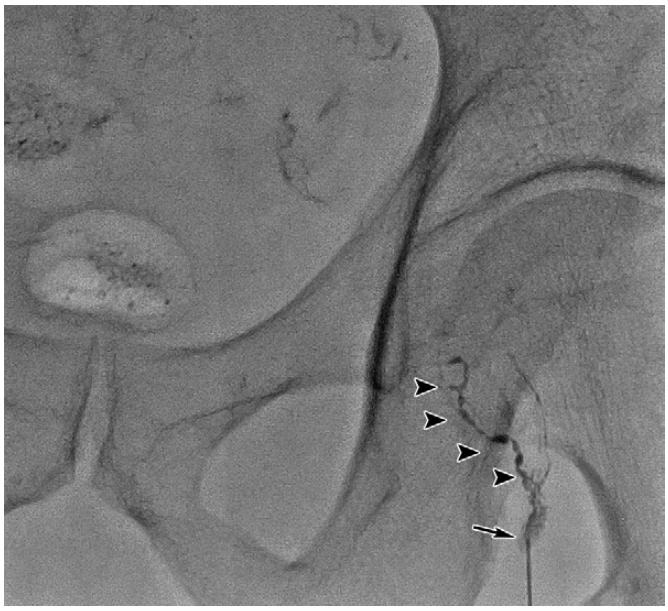

复发/难治性盆腔淋巴囊肿可尝试应用淋巴管栓塞术。在超声引导下,应用微穿针穿刺,微穿针远端置于淋巴结皮质与髓质之间,经微穿针缓慢注入超液化碘油,DSA密切监测淋巴管显影情况,必要时术中CBCT监测淋巴管显影。

DSA下淋巴管造影

当实时显影出现与淋巴囊肿相连接的淋巴管时即可进行栓塞治疗。淋巴管栓塞治疗术后仍需密切观察淋巴囊肿引流量。